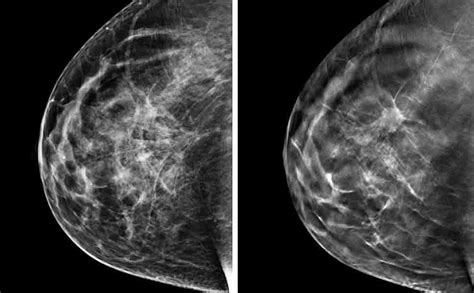

Parallelamente all'attenzione dedicata alla pelle, la mammografia rappresenta un pilastro fondamentale nella lotta contro il tumore al seno, una delle neoplasie più diffuse tra le donne. La mammografia è una tecnica di imaging a raggi X che permette di visualizzare l'interno del seno, identificando precocemente eventuali anomalie che potrebbero sfuggire alla palpazione.

La mammografia è in grado di rilevare:

- Noduli: masse solide o cistiche all'interno del seno.

- Microcalcificazioni: piccoli depositi di calcio che, a seconda della loro forma e distribuzione, possono essere indicatori di lesioni tumorali in fase precoce. La presenza di calcificazioni, in particolare quelle di aspetto "a grappolo" o lineari, è un segnale che richiede un approfondimento diagnostico.

- Distorsioni dell'architettura: alterazioni nella normale struttura del tessuto mammario.

La mammografia è uno screening efficace perché permette di individuare tumori in uno stadio molto precoce, quando sono più piccoli e più facilmente trattabili, aumentando significativamente le possibilità di guarigione e riducendo la necessità di trattamenti invasivi.